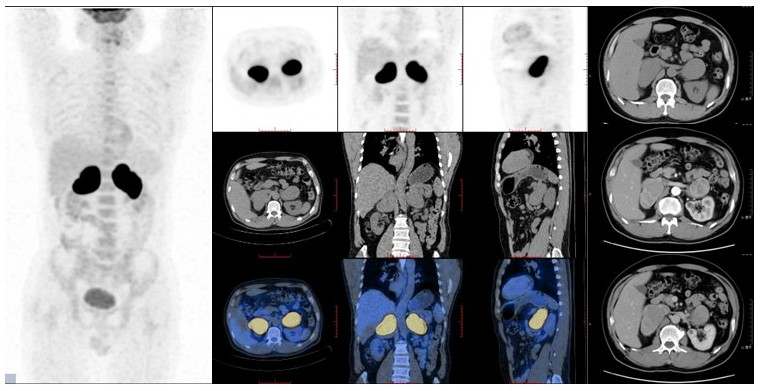

病例(11为一中年女性,体检发现右肾上腺肿物就诊;增强CT检查示右侧肾上腺区肿块,增强扫描呈明显不均匀强化伴多发小血管累及下腔静脉并突入腔内18F-FDG PET/CT示肿物代谢不均匀增高;肾上腺肿物)切除病理为平滑肌肉瘤

11. 52岁,体检发现右肾上腺肿物1平滑肌肉瘤